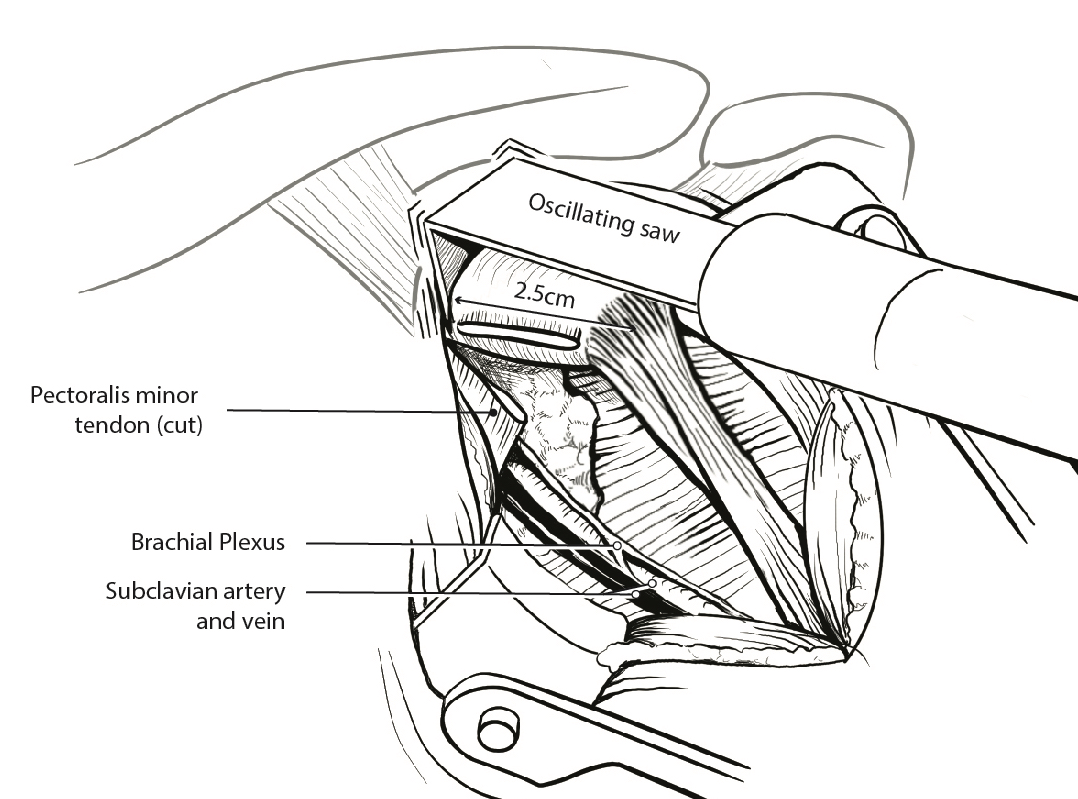

Coracoid osteotomy

- 2 cm coracoid osteotomy using 90o oscillating blade on microsagittal saw 100

- create bleed bone surface on posterior coracoid

- mobiize conjoint tendon, beware MCN 5 cm distal

Nerve injury

Enters conjoint tendon distally Avoid excessive dissection |

Vascular injury

- axillary artery injury